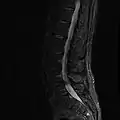

The fifth lumbar vertebra from above

The fifth lumbar vertebra is characterized by its body being much deeper in front than behind, which accords with the prominence of the sacrovertebral articulation; by the smaller size of its spinous process; by the wide interval between the inferior articular processes, and by the thickness of its transverse processes, which spring from the body as well as from the pedicles.[1] The fifth lumbar vertebra is by far the most common site of spondylolysis and spondylolisthesis.[3]